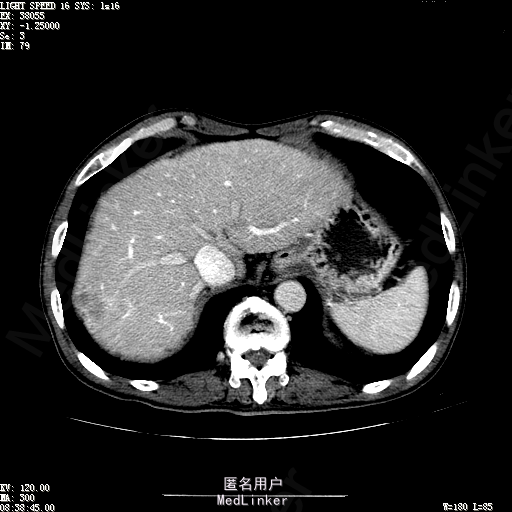

查体:体温36.3℃,脉搏76次/分,呼吸18次/分,血压120/80mmHg。神志清晰,肝病面容,皮肤粘膜颜色正常无黄染,全身皮肤未见皮疹、瘀点及紫癜,肝掌阳性,未见蜘蛛痣,浅表淋巴结未触及。巩膜无黄染,结膜正常。双肺呼吸音清,无胸膜摩擦音。心率:76次/分,心律齐,心音正常,无杂音,无心包摩擦音。腹平坦,无腹壁静脉曲张,未见胃肠型及蠕动波,双侧腹股沟可见手术瘢痕,脐部正常。触诊:无压及痛反跳痛,无腹肌紧张,无腹部包块。肝脾肋下未触及,Murphy征阴性,肾未触及,移动性浊音阴性。肝肾区叩击痛阴性,无脾区叩击痛。听诊:肠鸣音正常,4次/分,无气过水声。脊柱无侧弯,脊柱活动度正常,棘突正常,四肢正常,关节正常,无下肢水肿,无下肢静脉曲张,无杵状指趾。扑翼样震颤阴性。 门诊化验ALT9U/L,AST21U/L,HBVDNA<1.0E+03IU/mL,HBsAg1138IU/mL,WBC6.2x10^9/L,RBC3.92x10^12/L,PLT167x10^9/L,AFP28.95ng/ml,AFU 29U/L,彩超示肝右叶肝回声,大小约5.1*3.5cm,Fibroscan:脂肪变:163硬度10.8。 CT如下图

诊断:1、乙肝肝硬化 活动性 代偿期 原发性肝癌 2、胃溃疡 3、十二指肠球部溃疡 处理:血管介入治疗:手术者术前查看患者相关情况:化验回报:血细胞分析(五分类):*白细胞计数 8.1 10^9/L、*红细胞计数 4.00 10^12/L↓、*血小板计数 202.0 10^9/L、*血红蛋白 136 g/L,肝功酶谱:*丙氨酸氨基转移酶 5 U/L、天门冬氨酸氨基转移酶 22 U/L、*白蛋白 37.6 g/L、*总胆红素 17.8 umol/L,肾功能检测:*尿素 5.79 mmol/L、*肌酐 67.1 umol/L,凝血五项:凝血酶原时间 10.7 秒↓、凝血酶原百分活动度 93.3 %,甲胎蛋白测定:甲胎蛋白 30.30 ng/mL↑。患者病情平稳,今日术前准备,签署相关文件。 手术简要经过:患者平卧位,以右侧腹股沟区为中心常规消毒、铺巾、利多卡因局麻。改良Seldinger法逆行穿刺右侧股动脉成功,置入5F血管鞘。经血管鞘造影,见髂外动脉明显迂曲,经鞘送入超滑导丝,退出原5F血管鞘,换入5F长25厘米血管鞘。沿导丝送入肝管,将管头送入腹腔干,进一步送至肝右动脉。经正位、右前斜30°造影,明确肝右叶膈顶一处较大肿瘤染色,S5段一处较小肿瘤染色。以微导管超选S6段肝动脉干,经多角度造影明确为肿瘤供血动脉,注入混悬液(碘化油10毫升+雷替曲塞2毫克)3毫升,明胶海绵颗粒1/12支。再以微导管超选S7段肝动脉干,造影明确为肿瘤供血动脉,注入混悬液2毫升,明胶海绵颗粒1/20支。再以微导管超选S8段分支,造影明确为肿瘤供血动脉,注入混悬液2.8毫升,明胶海绵颗粒1/12支。再以微导管超选S5段肝动脉分支,造影明确为较小肿瘤供血动脉,注入混悬液0.8毫升,明胶海绵颗粒1/30支。退出微导管。经肝右动脉注入奥沙利铂100毫克。退出肝管。拔出血管鞘,局部压迫5分钟。加压包扎。